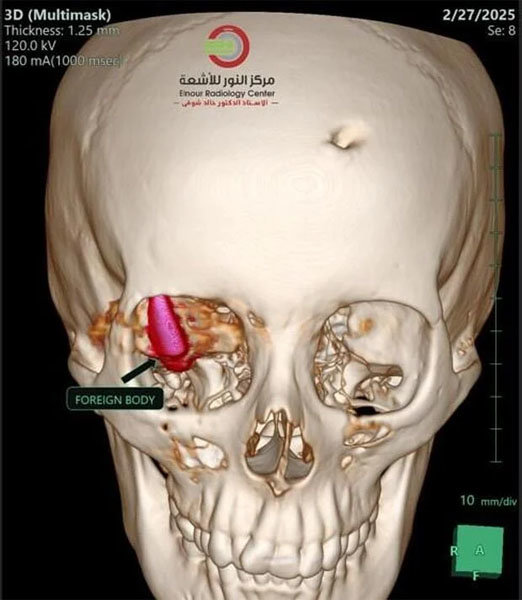

2023년 10월 7일 하마스의 테러 공격으로 가자지구에서 전쟁이 발발한 지 1년여가 지난 그곳엔 모든 것이 부족했다. 의사들은 열악한 환경에서도 최선을 다했다. 그들은 총알이 알-아와디의 오른쪽 눈 뒤쪽 두개골에 박혀 있다는 것을 확인했다. 하지만 제거할 능력이 없었다.

안과, 신경외과, 영상의학과 의사들이 팀을 이뤄 알-아와디의 시신경 바로 옆에 몇 달 동안 박혀있는 총알을 제거할 가장 좋은 방법에 관해 논의했다.

의료진은 시신경을 피해 총알을 제거할 수 있는 최적의 경로를 찾기 위해 가상 모의 수술을 수 차례 반복했다.

“총알은 환자에겐 가장 좋은 위치에 박혔지만 의료진에겐 최악인 곳에 있었다”라고 한 의사가 말했다. “어느 방향으로든 총알이 1mm만 움직였더라도 치명적인 피해를 피하지 못 했을 것”이라고 그는 부연했다.

의사들은 알-아와디의 뇌 손상을 피하기 위해 눈구멍을 통해 총알에 도달하는 게 최선의 선택이라는 데 동의했다.